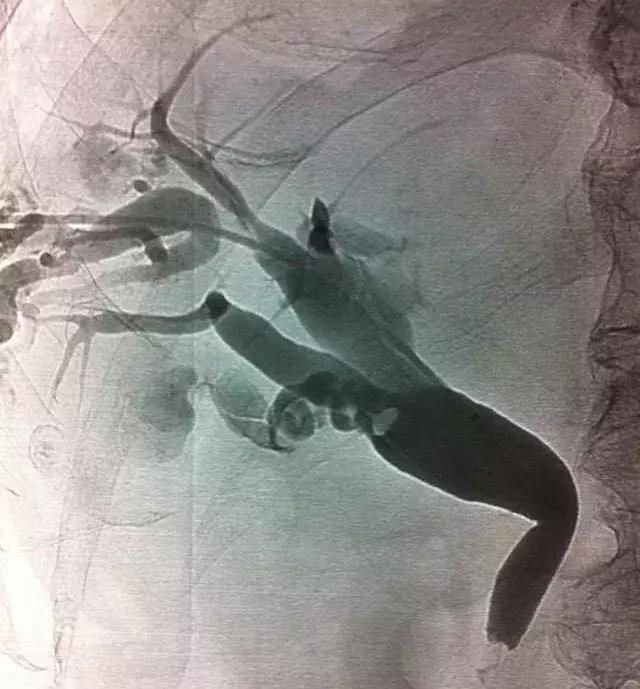

ERCP治疗

对于轻度或中度急性胆管炎伴胆管结石且无抗凝治疗或凝血功能异常的病人,可考虑在胆管引流的同时进行内镜下括约肌切开术(EST)清除结石,但EST常见的并发症有胰腺炎、十二指肠或胆管穿孔、出血和感染等,同时切开括约肌可能造成肠液返流,将来再次诱发胆管炎,因此有些医生选择气囊扩张壶腹部再行取石,这样能保留括约肌的功能。

对取石困难的病人,如结石较大或多发结石等,可以分两次进行:先行ENBD胆管引流,待炎症得到控制后再经内镜清除结石。

介入治疗

若因ERCP技术问题不能建立胆道引流,可通过经皮肝穿刺胆道引流(PTCD),如果胆管扩张不明显,另一个替代方法是经皮经肝胆囊穿刺引流(PTGD)。

PTCD治疗